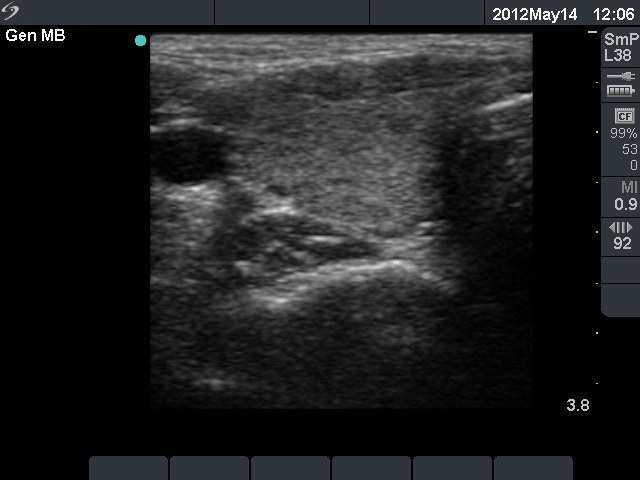

Follow-up investigation 2 years later (3rd row of images)

Clinical presentation: the complaints of the patient had decreased.

Palpation: no abnormality.

Functional state: euthyroidism with TSH-level 0.63 mIU/L, FT4 14.9 pM/L.

Ultrasonography: the thyroid became smaller. The echo pattern had not been changed on gray scale mode, but the vascularization had decreased.

We suggested follow-up examinations with yearly TSH determination in case of pregnancy.

Comment. The usual period of post partum hyperthyroidism is 5-10 weeks after delivery. Therefore in this patient the possibility of Graves' disease had to be considered. In such cases the FNAC may be of great help. This happened in this patient, cytology decided the differential diagnostic problem: the elevated FT4-level was caused by destruction and not by active hormone-producing disease.